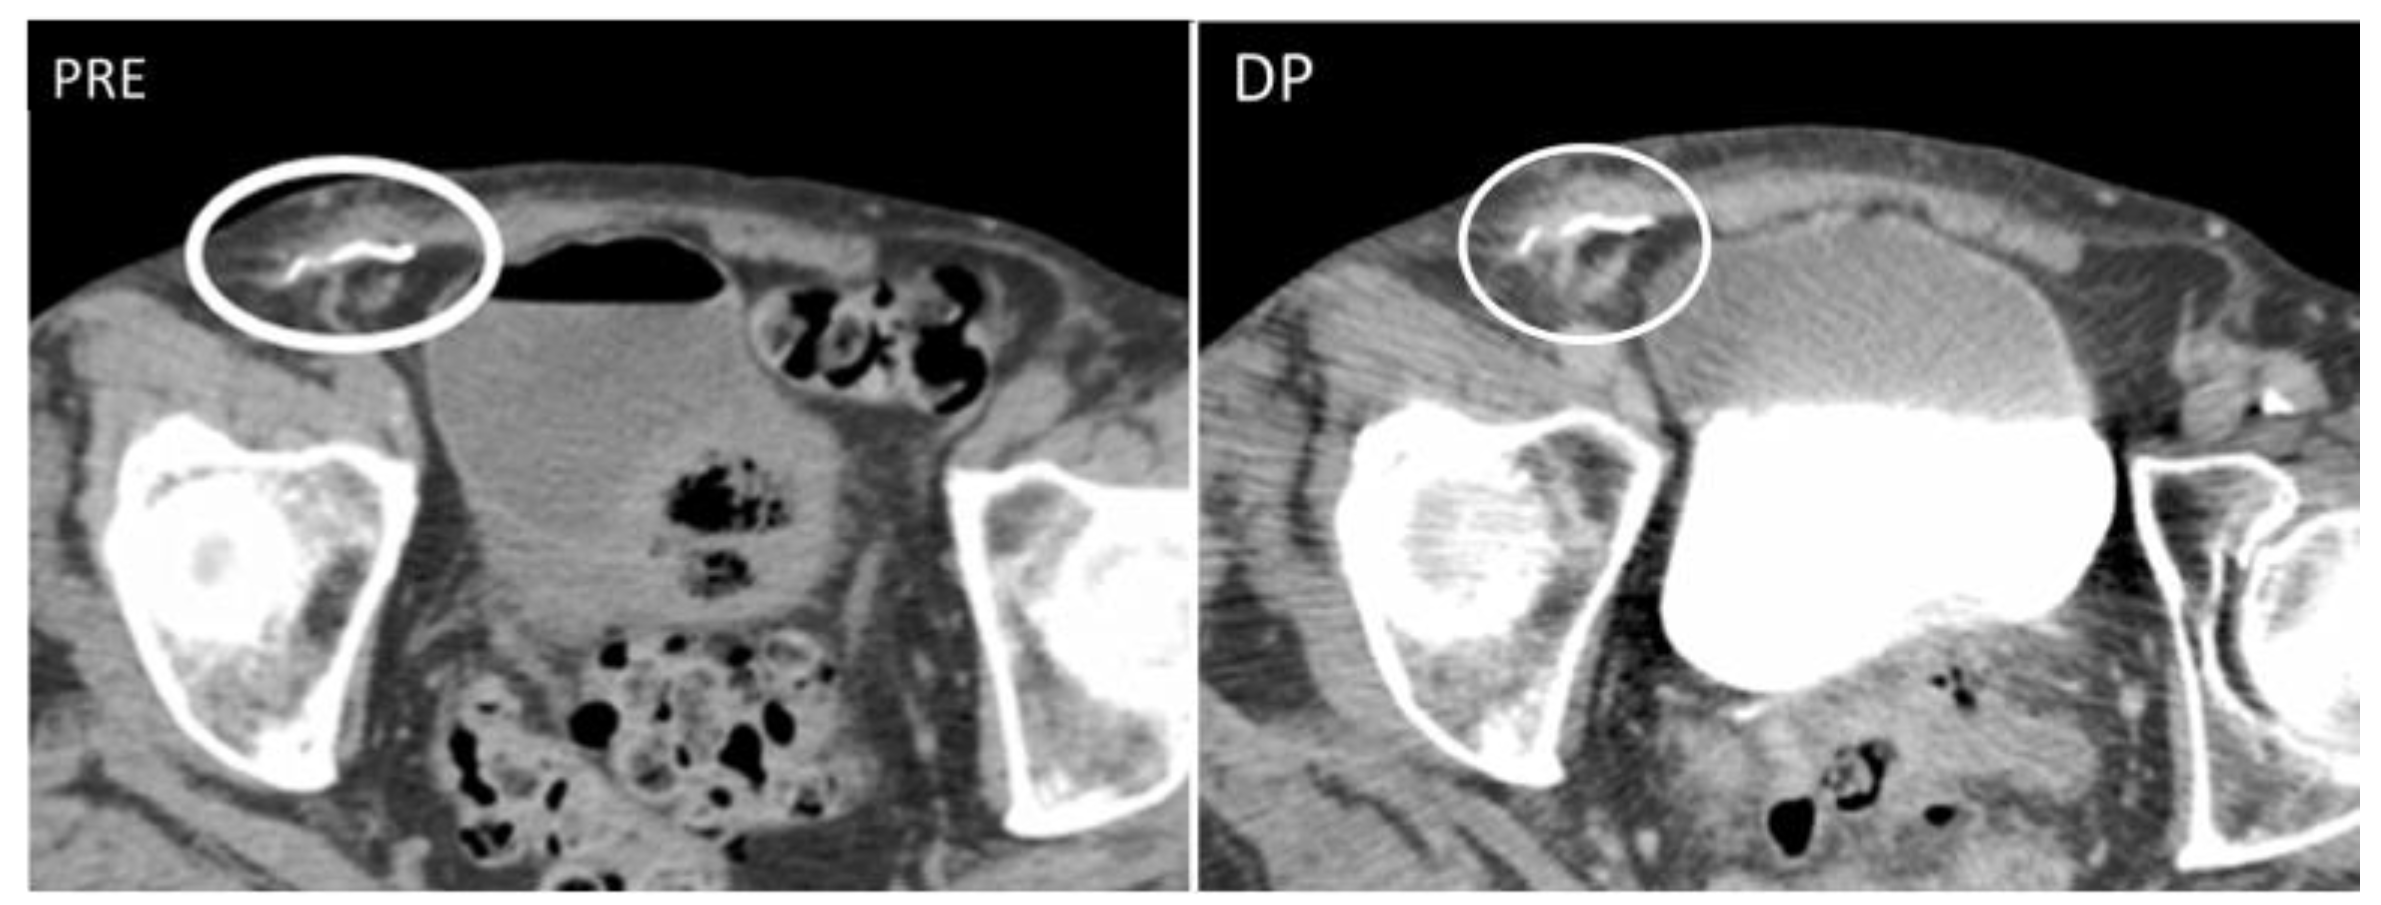

Pseudoaneurysms, or false aneurysms, originate from the disruption of intimal and medial layers of an arterial vessel, after traumas, infections, or iatrogenic procedures [30,31,32]. On US, pseudoaneurysms are anechoic tubular structures, with thin walls [30,31] and turbulent Doppler flow (“yin–yang” appearance).

CT angiography is the gold standard for the diagnosis, as it precisely depicts the vascular structures involved [31] and demonstrates the integrity of the pseudoaneurysm sac (Figure 9), which should be smooth unless an infection superimposes.

All pseudoaneurysms should be regarded as surgical urgencies, as they are considered at risk of rupture and therefore should be promptly treated to avoid bleeding [30]. Treatment includes ultrasound-guided thrombin injections and ultrasound compression, endovascular treatments with stent graft placement, and surgical repair. Among minimally invasive procedures, US-guided thrombin injection is usually preferred as it has a higher success rate compared to US-guided simple compression [33].

Figure 9. A 37-year-old man presenting with a pulsatile mass with trauma history. Volume rendering cutaneous reconstruction (A) and axial, contrast-enhanced portal-phase CT (B) showed the presence of a large post-traumatic pseudoaneurysm of the inferior right epigastric artery, with thrombotic apposition. B-mode US and CDUS (CE) demonstrate the presence of an anechoic part, corresponding to the contrast-enhanced part on CT, and the heterogeneity of the thrombus. CDUS (D,E) shows the “yin–yang sign”. The pseudoaneurysm was promptly treated with thrombin injection.